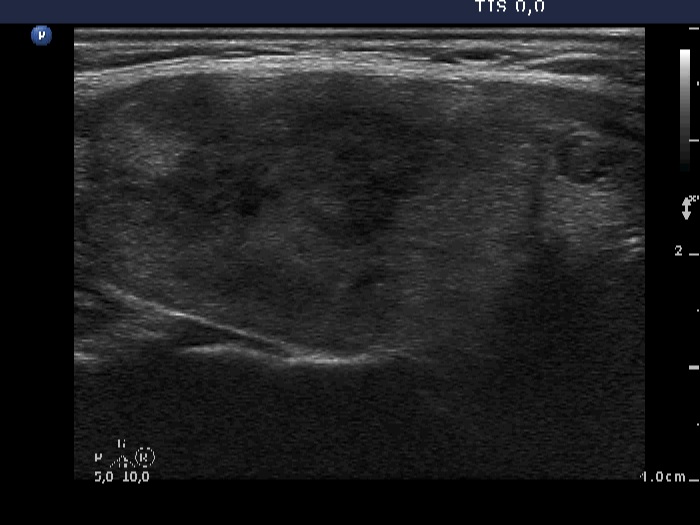

Examination 5 months later (3rd row of images):

Clinical presentation: within 24 hours of the administration of 32 mg methylprednisolone, the neck complaints and subfebrility had stopped and did not recur.

Palpation: the thyroids were minimally tender.

Laboratory tests: minimal degree of hypothyroidism (TSH 4.08 mIU/L, FT4 11.5 pM/L), CRP 0.7 mg/L.

Ultrasonography: the thyroid decreased in size as did the extent of hypoechogenic areas. The vascularization was unchanged. There was a cystic lesion presenting microcalcification in the solid part in the lower part of the right lobe. We reviewed the video of the first examination and noticed that the lesion was already present but much smaller. The difference in size was explained by the lack at cystic component at first investigation.

Cytology from the cystic lesion in the right lobe resulted in papillary carcinoma.

Total thyroidectomy was performed. Histopathology discloses a papillary carcinoma. It was solitary with a 4 mm maximal diameter. The left lobe displayed no abnormality.